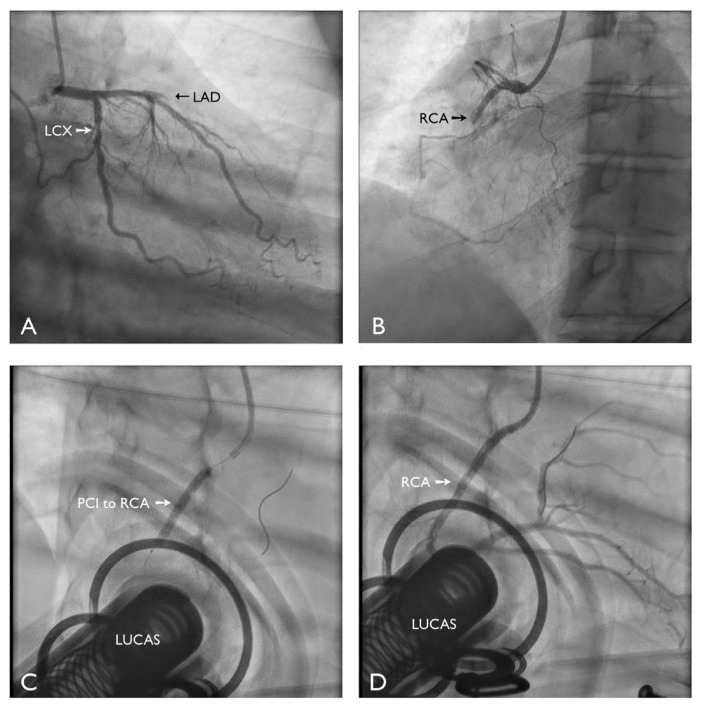

我们报告一例男性急性下壁心肌梗死患者,在长时间心脏骤停(220分钟)期间接受了成功的初级冠状动脉介入治疗,并使用机械胸部按压装置进行了持续复苏。他的神经系统完全恢复了。在这种情况下,机械压迫装置可能有助于维持灌注并改善预后。

We report a case of a male patient with an acute inferior myocardial infarction who underwent successful primary coronary intervention during prolonged cardiac arrest (220 minutes) and continuous resuscitation using a mechanical chest compression device. He achieved full neurological recovery. Mechanical compression devices may help maintain perfusion and improve outcomes in such scenarios.